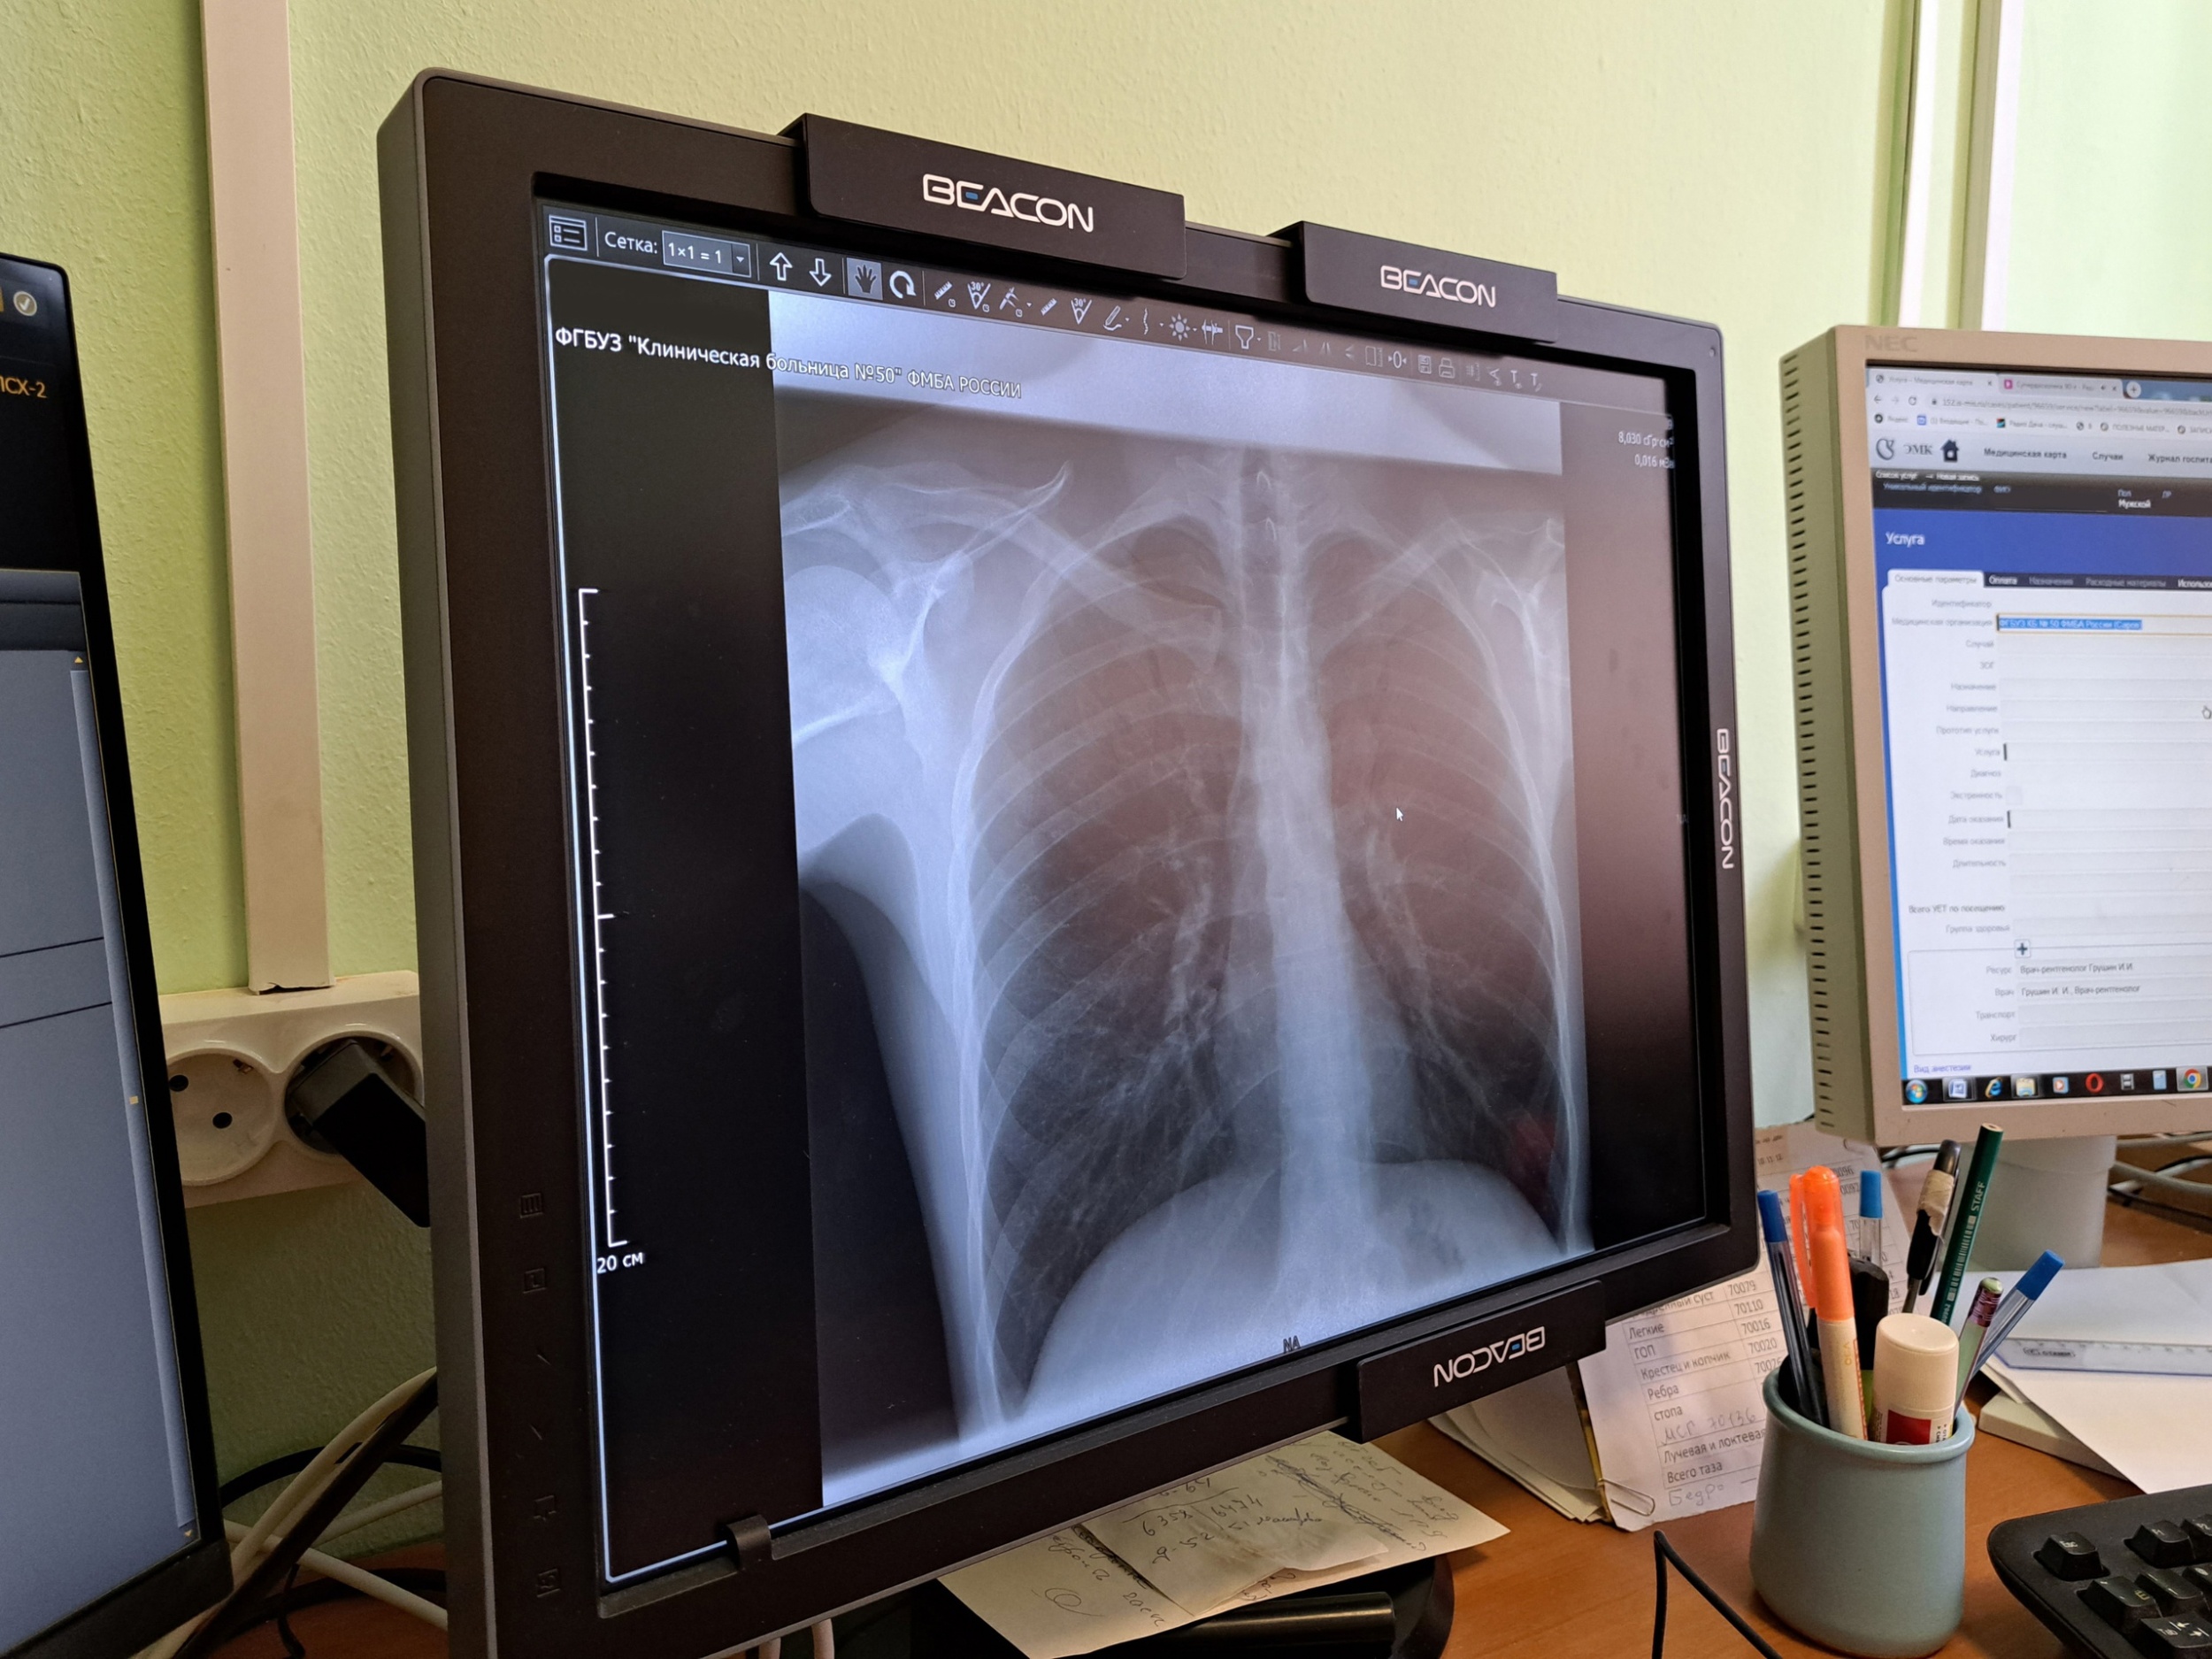

В КБ-50 закуплен цифровой рентген вместо плёночного

Недавно в распоряжение КБ-50 поступил современный цифровой рентгенодиагностический комплекс на три рабочих места. «Он позволяет проводить рентгенографию и рентгеноскопию. Мы можем диагностировать заболевания органов грудной клетки и брюшной полости, суставов, костей, позвоночника. Сама процедура проходит намного быстрее, чем на старом, пленочном оборудовании и занимает в среднем 5 минут, что удобно как для лаборанта, так и для врача. Если раньше мы делали снимок, затем его проявляли и только потом приступали к описанию, то сейчас вся информация сразу передается на компьютер», — рассказал врач-рентгенолог Иван Грушин.

«Снимки получаются очень высокого качества. Я могу подстроить под себя яркость и контрастность, рассмотреть мелкие детали. Аппарат оснащен современным программным обеспечением, которое помогает быстро и точно проводить диагностику, вести протоколы исследований. Снимки сохраняются в электронном виде в информационной системе и врач, который направил к нам пациента, может сразу увидеть результаты. При необходимости есть возможность записать их на диск», — рассказал врач-рентгенолог Иван Грушин.